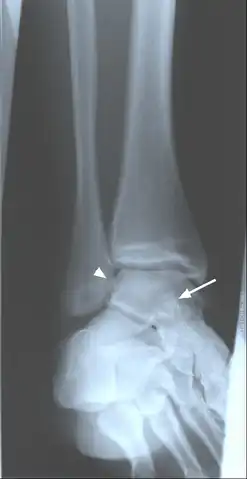

Oblique ankle radiograph with evidence of calcified loose bodies medial arrow head to the lateral maleolus and superimposed over the talus arrow, this suggests synovial chondromatosis